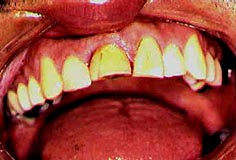

Clínicamente el 1.1 se observa tanto en vestibular como palatino una corona con poca estética (fig. 2 y 3)

Fig. 2 Vista vestibular, corona con poca estética

Fig. 3. Vista palatina de 1.1, corona con poca estética.